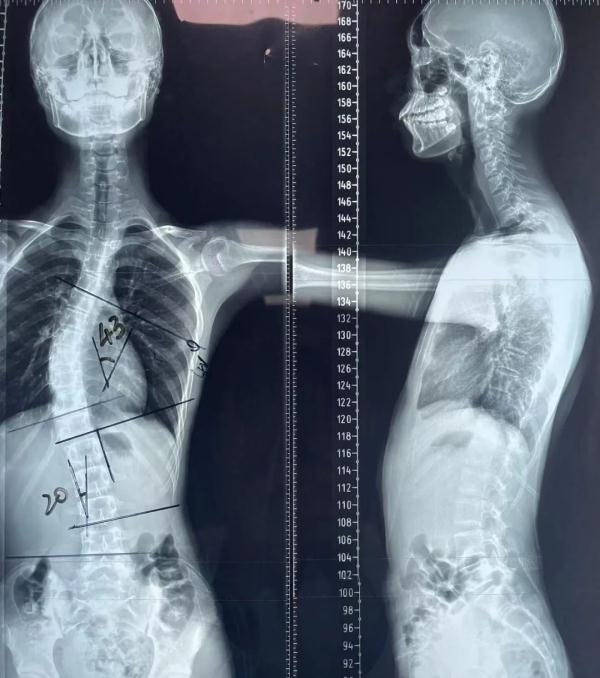

几个月前,家人发现乐乐的后背左右两侧高度不一样。去年12月,父母带着乐乐慕名找到了中国科大附一院(安徽省立医院)的张文志教授。张文志团队为乐乐完善了相关检查,“全脊柱正侧位X线片检查提示为脊柱侧弯,达到43度,一般超过40度,就需要手术治疗。”

据介绍,脊柱侧弯手术难度较高,风险相对于其它常规手术也更大。像乐乐这样的青少年,椎体旋转程度重,双侧椎弓根发育不对称,对手术的精度要求也更高。经过讨论,张文志和团队决定采用脊柱外科手术机器人为乐乐进行矫正。“相比传统脊柱手术,出血量少、神经损伤风险小。”